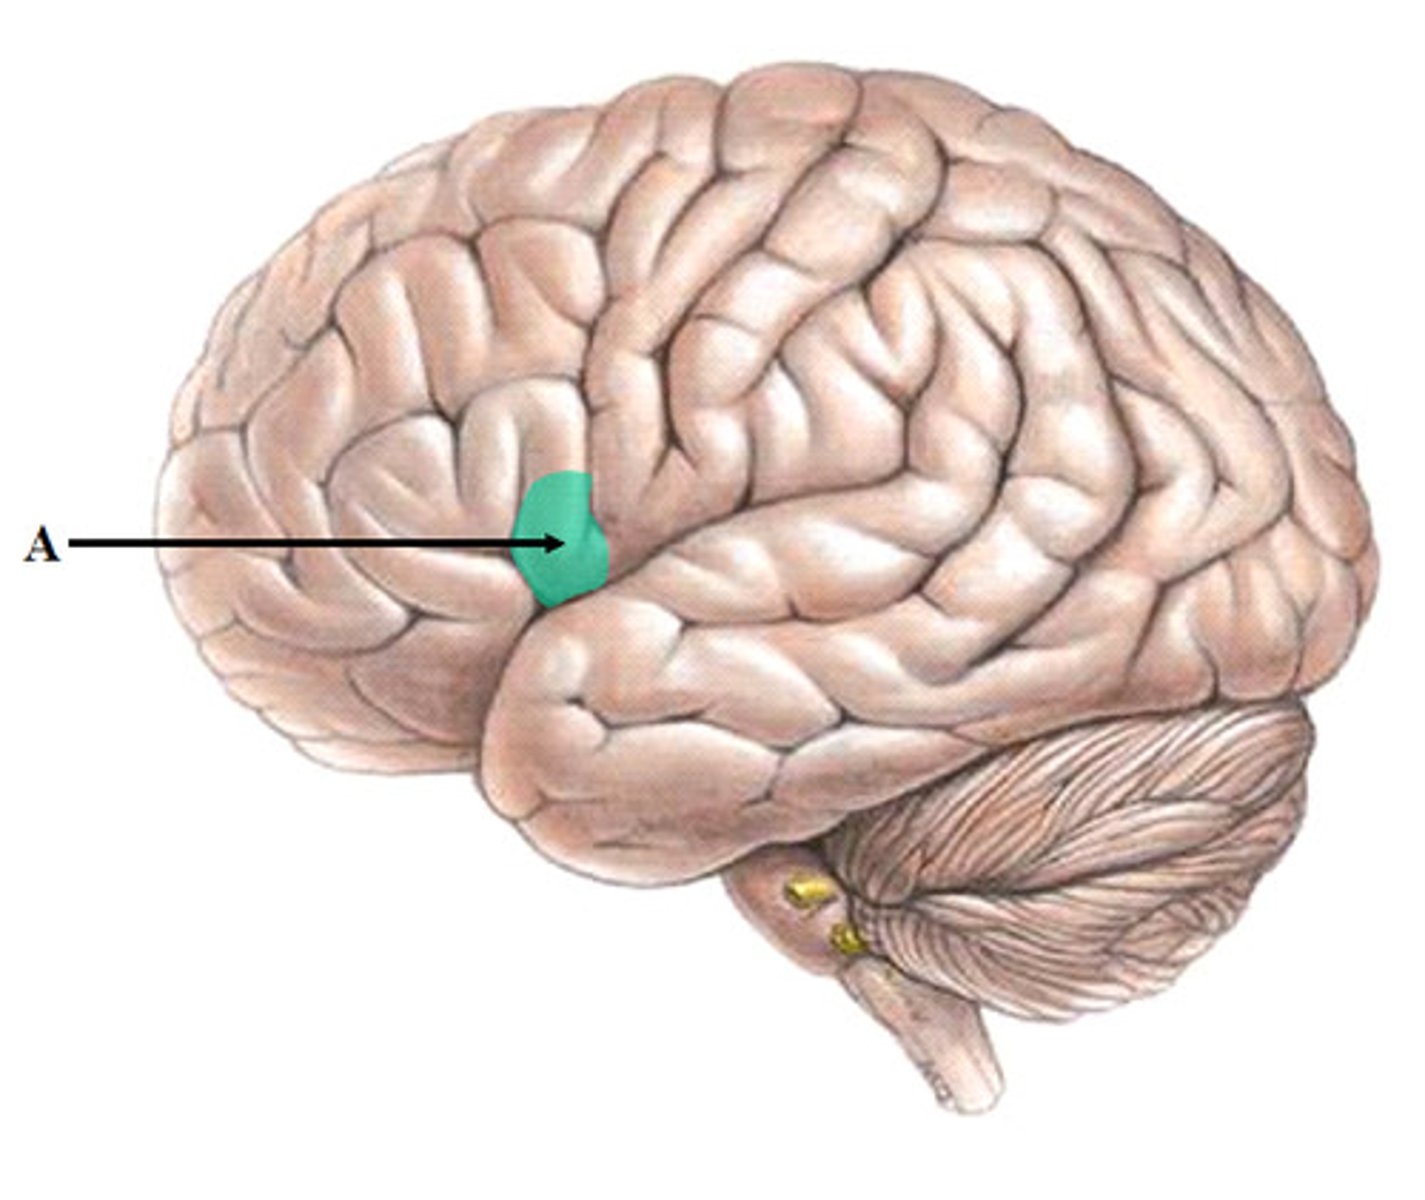

Broca's area

Controls language expression - an area of the frontal lobe, usually in the left hemisphere, that directs the muscle movements involved in speech.

<p>Controls language expression - an area of the frontal lobe, usually in the left hemisphere, that directs the muscle movements involved in speech.</p>